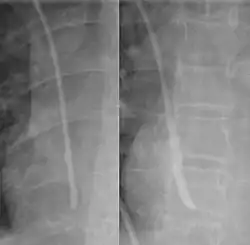

The line is then inserted using the Seldinger technique: a blunt guidewire is passed through the needle, then the needle is removed. A dilating device may be passed over the guidewire to expand the tract. Finally, the central line itself is then passed over the guidewire, which is then removed. All the lumens of the line are aspirated (to ensure that they are all positioned inside the vein) and flushed with either saline or heparin.[1] A chest X-ray may be performed afterwards to confirm that the line is positioned inside the superior vena cava and no pneumothorax was caused inadvertently. On anteroposterior X-rays, a catheter tip between 55 and 29 mm below the level of the carina is regarded as acceptable placement.[37] Electromagnetic tracking can be used to verify tip placement and provide guidance during insertion, obviating the need for the X-ray afterwards.

Chest x-ray with catheter in the right subclavian vein -